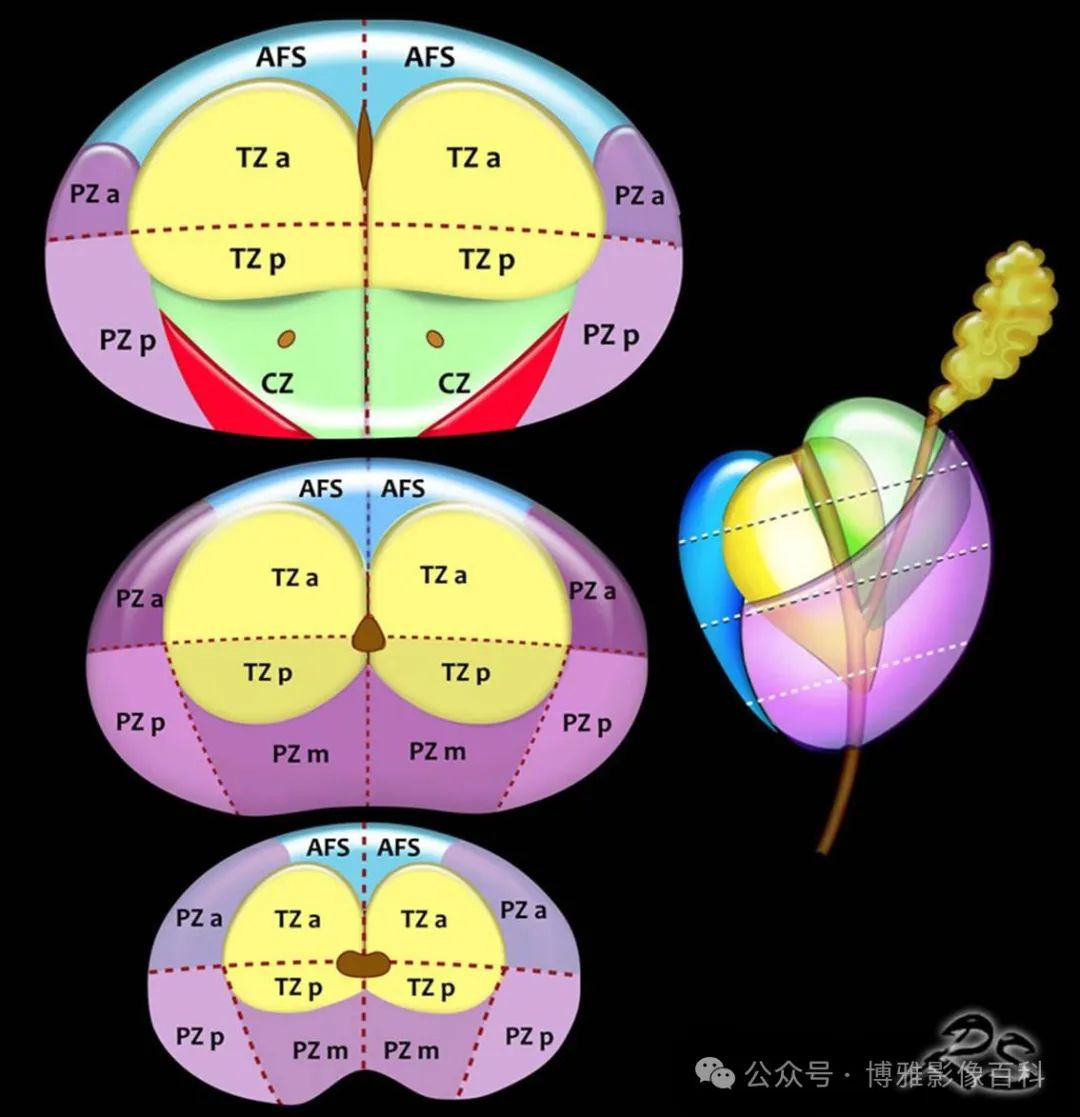

扇区解剖

PI-RADS 第 2 版中使用的扇区图使用了 39 个扇区(14 个在基底部,12 个在中部,12 个在前列腺尖部,2 个精囊和 1 个尿道括约肌)。在 2.1 版中,为基底部的左右后内侧 PZ (PZpm) 增强加了两个额外的扇区(见下图,红色)